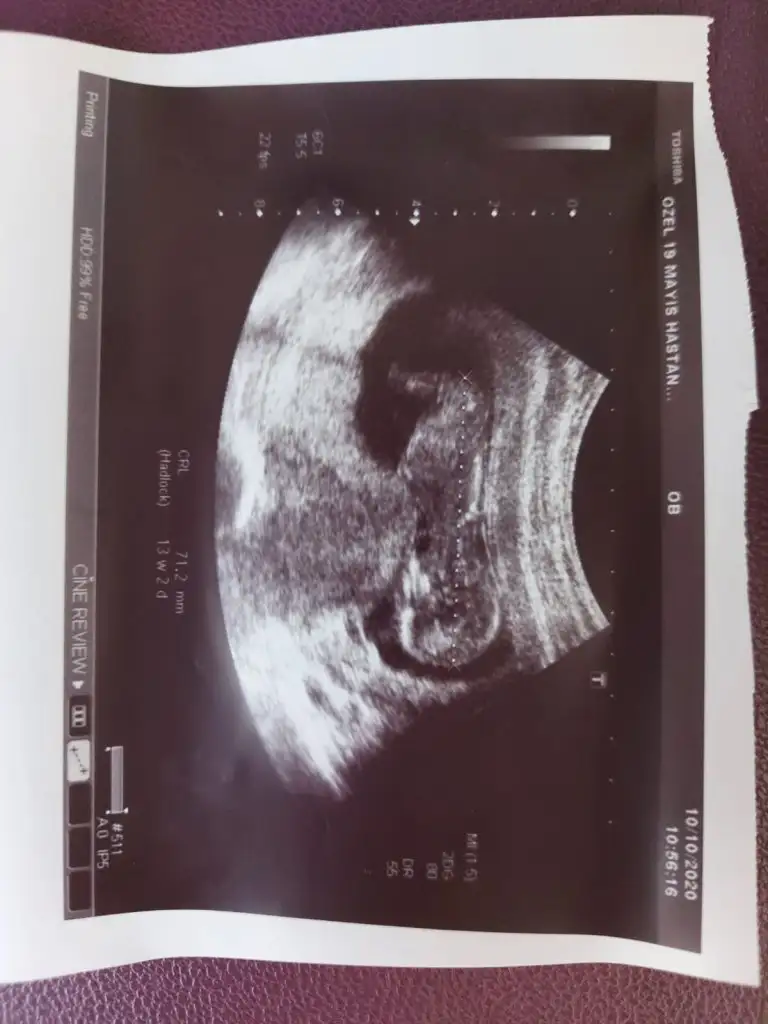

Daha küçükMerhabalar, bu ultrason fotografina gore cinsiyet tahmininiz var midirkalbi 6+4 de 150 atiyordu simdi 9+4 gozuktu bir hafta onden gidiyormus 180 atiyordu. Bir de sag tarafa yerlesmis

Olursa paylaşın 11 12 13 haftalar olur hiç net değil kız dedim ama olmayabilir net değil ilk bebekmi

Kız gibi sanki 14 haftada nub olmaz ama sanki diklik olsa yada pipi olsa görünürdüEki Görüntüle 2703543 14 Haaftalık şuan nub a göre yorumlarmısınız